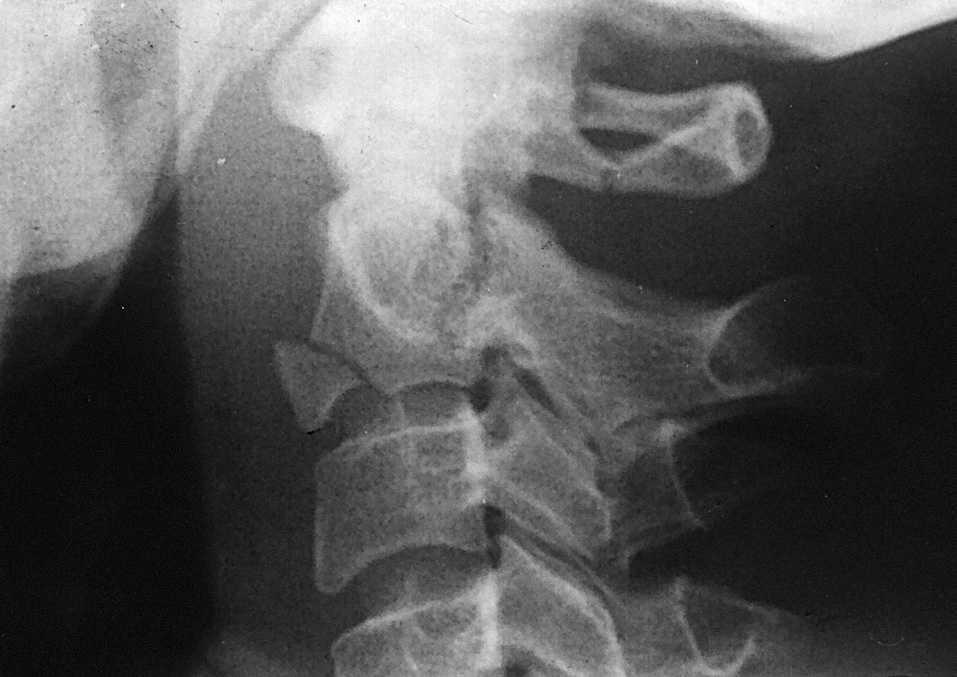

El diagnóstico se hace mediante radiografías en proyección lateral (fig. 11) o transbucal. La TAC es útil para dar detalles de la lesión ósea. La existencia de síntomas neurológicos es rara; en nuestra serie sólo los tuvieron 2 de 9 pacientes (22,2%).

Figura 11. Fractura en lágrima asociada a fractura del ahorcado y fractura del arco posterior de CI.